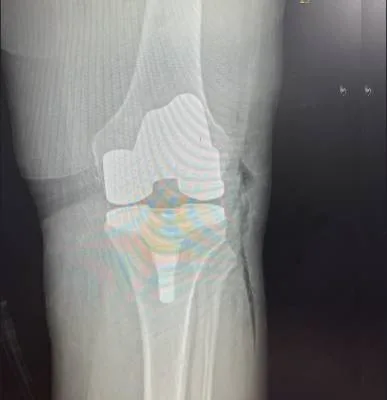

I had surgery with Dr. Haytham, and I’m very happy with the results. He previously operated on my leg after a fracture, and that surgery was very successful. Recently, I had another surgery on my knee, which was done in the simplest and most professional way. After the operation, I was able to return to my normal life — I can play football and be active again after a long time of not being able to. Dr. Haytham and his team took great care of me throughout the process, and I truly thank him for his excellent work and dedication